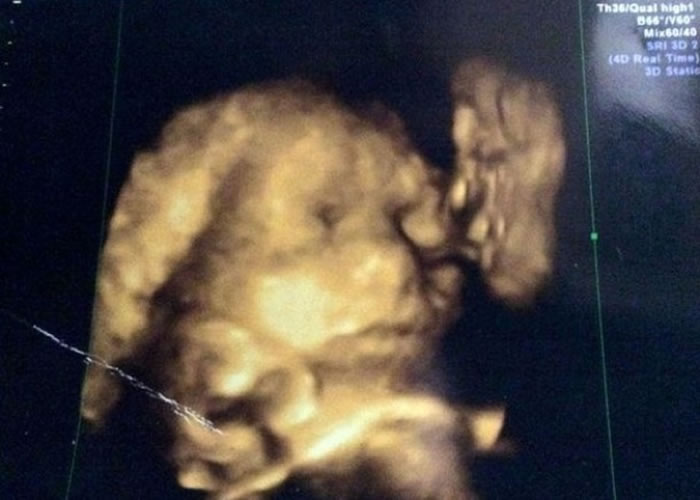

英国怀孕准妈妈4D超声波照 子宫内惊现去世曾祖父吻曾孙

4D超声波照片(左图)中惊见,已去世的霍恩斯比(右图)噘起嘴在亲吻曾孙。

(蜘蛛网报道)英国东伦敦一名怀孕30周的准妈妈,之前到医院为腹中胎儿照4D超声波,想看看未来女儿长什么样子。岂料,当她回到家中看到照片时,她完全惊呆了,原因是她在照片中竟看见已去世的爷爷,噘起嘴在亲吻胎儿。

21岁的杰德(Jade Hornsby)说:“这真吓人。这太像他了。你可以看他的轮廓比我女儿还清楚。你可以清楚看见他的眼睛、鼻子和嘴巴。而他噘起嘴唇,似乎是在亲吻婴儿的脸颊。”

杰德的爷爷霍恩斯比(Jack Hornsby)已于2007年去世。当杰德将超声波照片拿给母亲看时,她立刻认出这是霍恩斯比的脸。杰德称:“我很开心,我跟爷爷有许多美好的回忆。我相信这是爷爷在天之灵的祝福。”